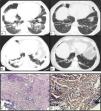

We report a case of a 69-year-old man, former smoker (70 pack-years), with occupational exposure to dust and fumes from metallurgical casting and contact with birds, who presented to the emergency department with a 6-month history of progressive dyspnea. He reported mild fever, anorexia, and weight loss (10 kg over the prior 3 months). A physical examination revealed inspiratory crackles in the lower lungs. Chest computed tomography (CT) scan showed bilateral peripheral consolidation areas, mainly in the lower lobes but also involving the middle lobe and lingula (Fig. 1 — A and B); the CT also revealed hepatosplenomegaly. Laboratory data demonstrated normocytic and normochromic anemia, and elevated levels of C-reactive protein and erythrocyte sedimentation rate. An autoimmunity study was negative. No endobronchial lesions were detected in the bronchoscopy. In the bronchoalveolar lavage, the total and differential cell counts revealed lymphocytic (47%) and neutrophilic (7.4%) alveolitis, which was negative for microorganisms and malignant cells. An initial pulmonary function test revealed moderate restrictive ventilatory alteration with a forced expiratory volume in one second (FEV1) 2.06 L (72.8% of the predicted value), forced vital capacity (FVC) 2.42 L (65.6%), preserved FEV1/FVC ratio, a total lung capacity (TLC) 4.51 L (68.5%), and carbon monoxide transfer factor (TLCO) 52%. A CT-guided transthoracic core biopsy was subsequently performed, and hyalinized lamellar collagen tissue surrounded by lymphoplasmacytic infiltrates was reported on histological examination (Fig. 1E1). No evidence of neoplastic cells was found, and acid-fast, fungal, and Congo red stains were all negative (Fig. 1E2). These findings were consistent with a diagnosis of PHG. The patient was started on oral corticosteroid therapy (deflazacort in an equivalent dose of 0.5 mg/kg/day of prednisolone, within a weaning scheme) and demonstrated partial clinical and functional but not radiological improvement.

Chest CT scan showing bilateral peripheral consolidation areas in the lower lobes before (A and B) and after (C and D) complete chemotherapy scheme. (E1) Histology showing hyalinized lamellar collagen tissue surrounded by lymphoplasmacytic infiltrates (hematoxylin and eosin, ×200); and (E2) negative Congo red stain (CR, ×200).

Throughout the investigation, an indolent non-Hodgkin’s lymphoma (NHL) was incidentally diagnosed, supported by a bone marrow biopsy. The clinical case was, therefore, discussed in a multidisciplinary team, and with PHG hypothesized as a paraneoplastic manifestation of hematological disease, a decision to start NHL treatment was made. After completing eight cycles of chemotherapy (rituximab, cyclophosphamide, vincristine, and prednisolone), the patient had significant clinical, functional, and radiological improvement (Fig. 1 — B and D). At the time this report was written, the patient was asymptomatic and functional with FEV1 2.88 L (106.5%), FVC 3.66 L (103.1%), TLC 5.83 L (89.7%), and TLCO 68%. No residual disease was found on further bone marrow tests.